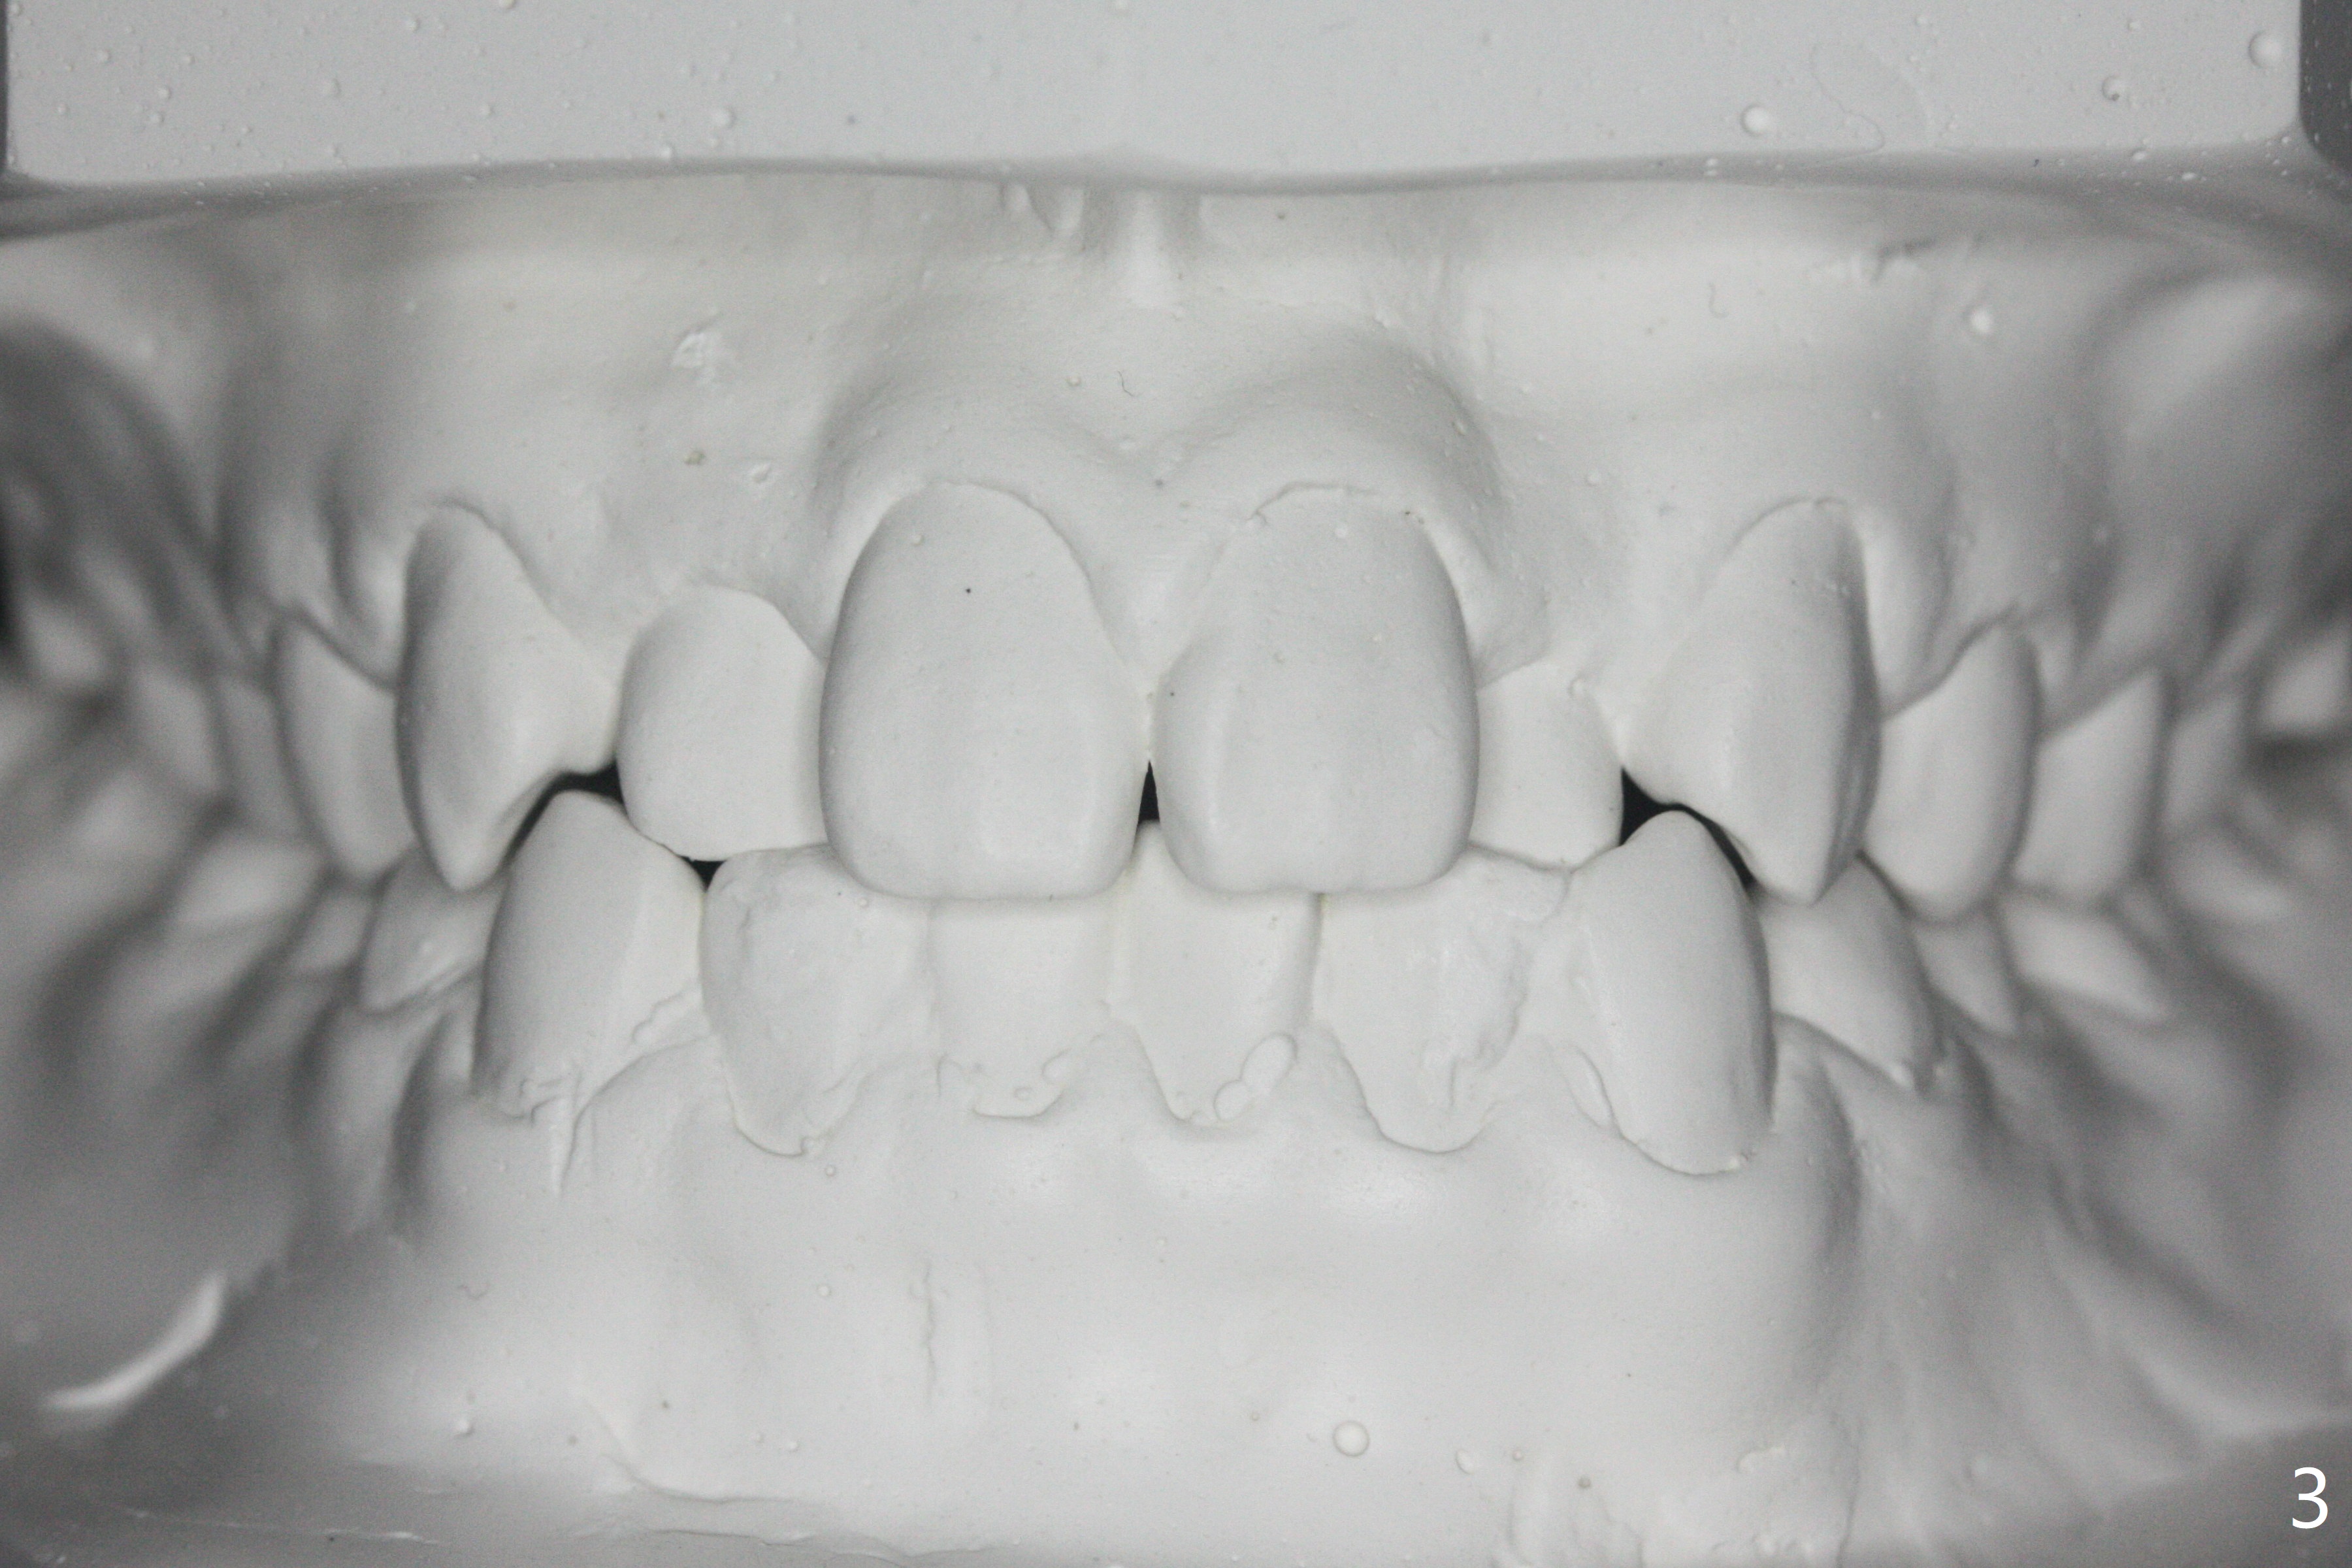

15岁男完成矫正1年9月,右侧后牙咬合理想(图二),上中切牙长轴改善,侧切牙torque不够完善(图四),左侧后牙咬合二类𬌗(图六,需要牵引),磨牙缝隙大(图八,十),造成食物堵塞,以后尽量避免使用磨牙bands,尤其是成人。